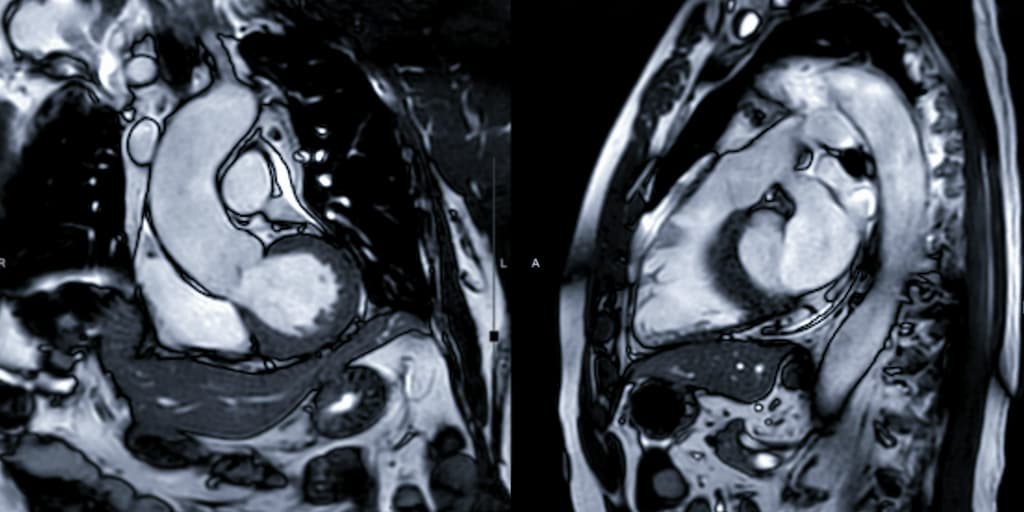

CMR Radiomics

CMR radiomics is an emerging technique that extracts features from radiographic medical images using data-characterisation algorithms for deeper cardiac phenotyping. CMR may be used to detect early changes in the shape and tissue texture of the heart due to risk factors including cigarette smoking (past and current), hypertension, high cholesterol, and diabetes.

Existing MRI methods use detailed scans and simple measurements of the hearts main pumping chambers but may not always detect early changes related to disease. Radiomics analysis of images is highly detailed and produces hundreds of numerical measurements of the heart.